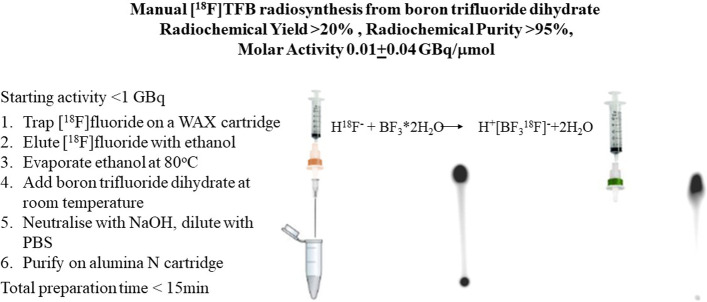

In the same year a CRUK Cambridge Institute group (Soloviev et al. 2016) reported a manual radiolabelling procedure of the easily accessible commercial reagent boron trifluoride dihydrate, thus simplifying the synthetic procedure (20–40% overall radioactivity yield in 15 min), but the molar activity of the final preparation was surprisingly low (0.01 ± 0.04 GBq/µmol at EOS).

Direct addition of [18F]fluoride to boron trifluoride dihydrate proceeds instantly at room temperature with more than 80% [18F]fluoride incorporation, as monitored by thin layer chromatography (Soloviev et al. 2016) (Fig.1). The fast reaction rate is predictable, given the ionic nature of the boron trifluoride dihydrate (Wamser 1951):

Fig. 1.

Manual radiolabelling procedure of boron trifluoride dihydrate (adapted with permission from Soloviev et al. (Soloviev et al. 2016))

Low molar activity of the [18F]TFB prepared from boron trifluoride dihydrate (median Am 0.01 ± 0.04 GBq/µmol at EOS) could not be attributed only to low starting fluoride activity (< 1GBq). The high mass of the non-radioactive tetrafluoroborate present in the final preparation could be explained by the multi-step hydrolysis of boron trifluoride upon addition of water (Wamser 1951) providing tetrafluoroborate and boric acid in the following summary equation, Fig.2:

Of note were low radioactivity yields achieved after purification (in the range of 20–30%) despite a short radiosynthesis time (less than 15 min) and high [18F]fluoride incorporation into [18F]TFB (Fig. 1). This observation corroborated well with other reports (Khoshnevisan et al. 2016; Jauregui-Osoro et al. 2010; Jiang et al. 2016), when low radiochemical yields, despite the high fluoride incorporation, could be attributed to the use of two large format alumina purification cartridges for fluoride removal—refer to (Khoshnevisan et al. 2016) and the "Discussion" section below.